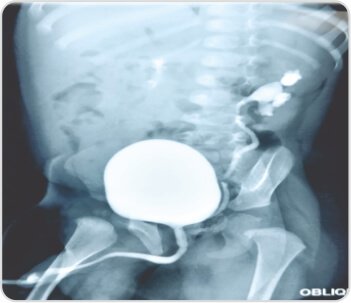

On evaluation, he was found to have complete left duplex kidneys with upper moiety moderate hydro-ureteronephrosis with ectopic insertion into prostatic urethra with good parenchyma and excretion on CT Urogram. MCUG showed low grade reflux into lower moiety. DMSA scan showed reduced upper moiety function.

Robotic left-sided Uretero-Pyelostomy was done. Dilated upper moiety ureter was transected and anastomosed to lower moiety pelvis in end to side fashion. DJ stent was placed across the anastomosis into the upper moiety ureter. Post operative period was uneventful and the stent was removed after 6 weeks.